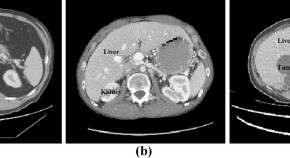

Artificial Intelligence-Powered Clinical Decision Support and Simulation Platform for Radiology Trainee Education